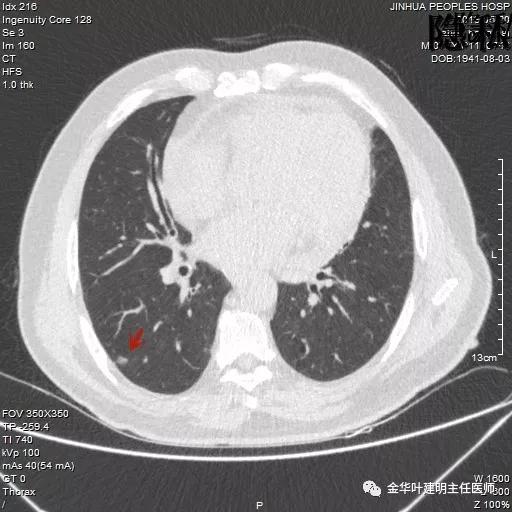

金华的周某,今年已经78岁了,上个月底单位退休人员体检,查出他的右肺有一结节,结果出来后,这个月通知他到胸外科复诊。因为是我的亲戚,便直接找到了我,我从电脑里调出他的CT片,如下所示:

可见其右下叶有一空腔性病灶,壁薄,病灶下方见到实性密度的成份。我们看过目前的片子后,马上想到的是此病灶以前有没有,对比是非常重要的。调出之前片子: